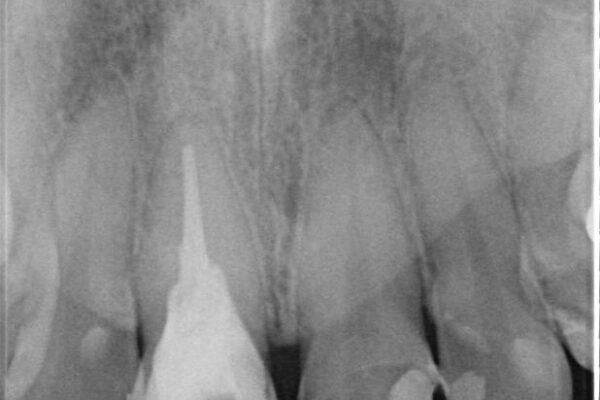

治療前

• 「抜歯してブリッジ」と言われた20代女性が選んだ治療とは|たった4か月で自然な笑顔に抜歯即時インプラント+審美補綴の症例 治療前画像

精密検査の結果、右上中切歯には**フェルール(歯の周囲の健全な歯質)**がほぼ存在せず、このままの状態での保存は困難と判断しました。

■保存治療の選択肢として**挺出(エクストリュージョン)**により歯を引っ張り出し、フェルールを確保する方法も検討可能でしたが、患者様のご希望により、より短期間で審美性を回復できる治療法を選択。